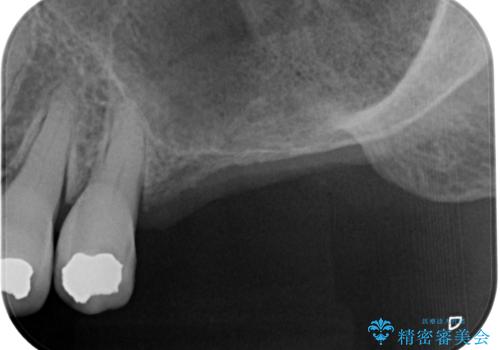

- 精密根管治療

- 2012~2025年6月

- 000歯

最新の症例

Latest cases